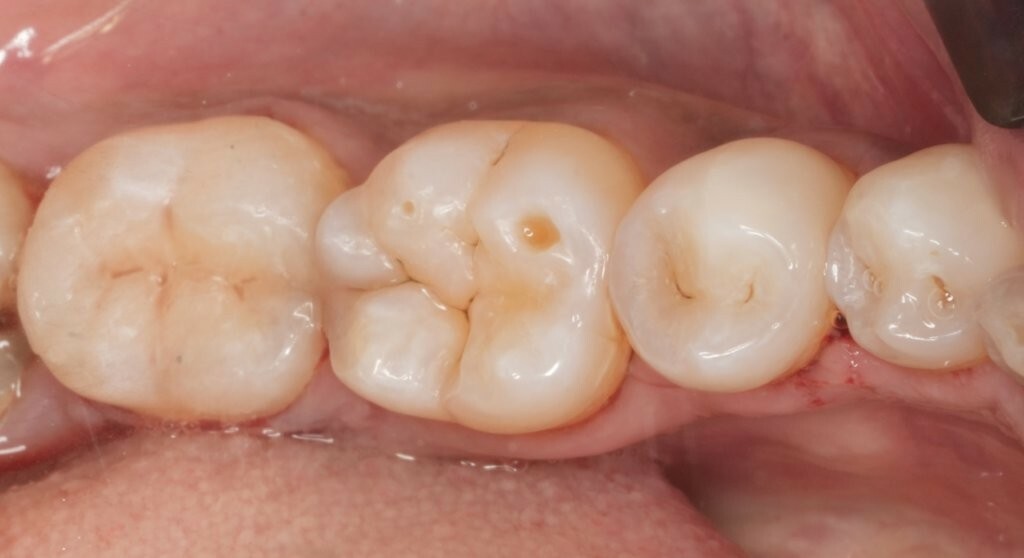

Abbildung 1: Ausgangssituation. Initiale klinische Präsentation einer ausgeprägten, kavitierten, kariösen Läsion an Zahn 37, mit Symptomen einer reversiblen Pulpitis.